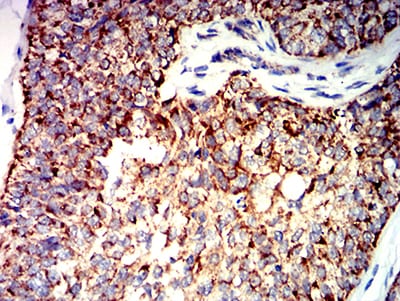

分类: 科研抗体货号: 31278别名: CTNNB; MRD19; armadillo;Beta-catenin应用: WB,IHC,FCM反应种属: Human